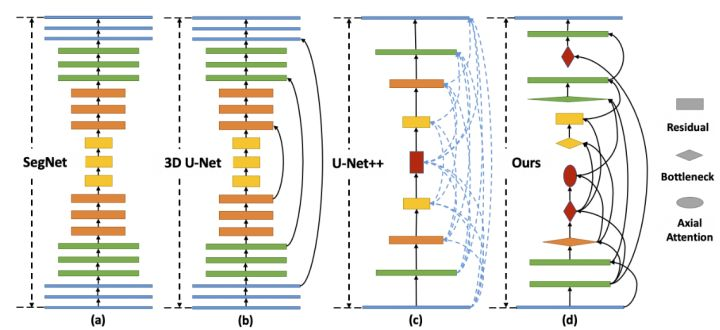

U-Net++

Paper: 《UNet++: Redesigning Skip Connections to Exploit Multiscale Features in Image Segmentation》

Accepted by TMI 2019.

文章解读:https://zhuanlan.zhihu.com/p/44958351

U-Net++ 的第一个优势就是精度的提升,通过整合不同层次的特征加强信息交互;第二个是灵活的网络结构配合深监督,让参数量巨大的深度网络在可接受的精度范围内大幅度的缩减参数量。